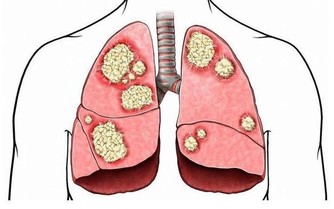

長期大量飲酒,在初期表現為酒精性脂肪肝,之後會進一步發展成酒精性肝炎、酒精性肝硬化,

可能還會得慢性酒精中毒,增加肝癌風險。